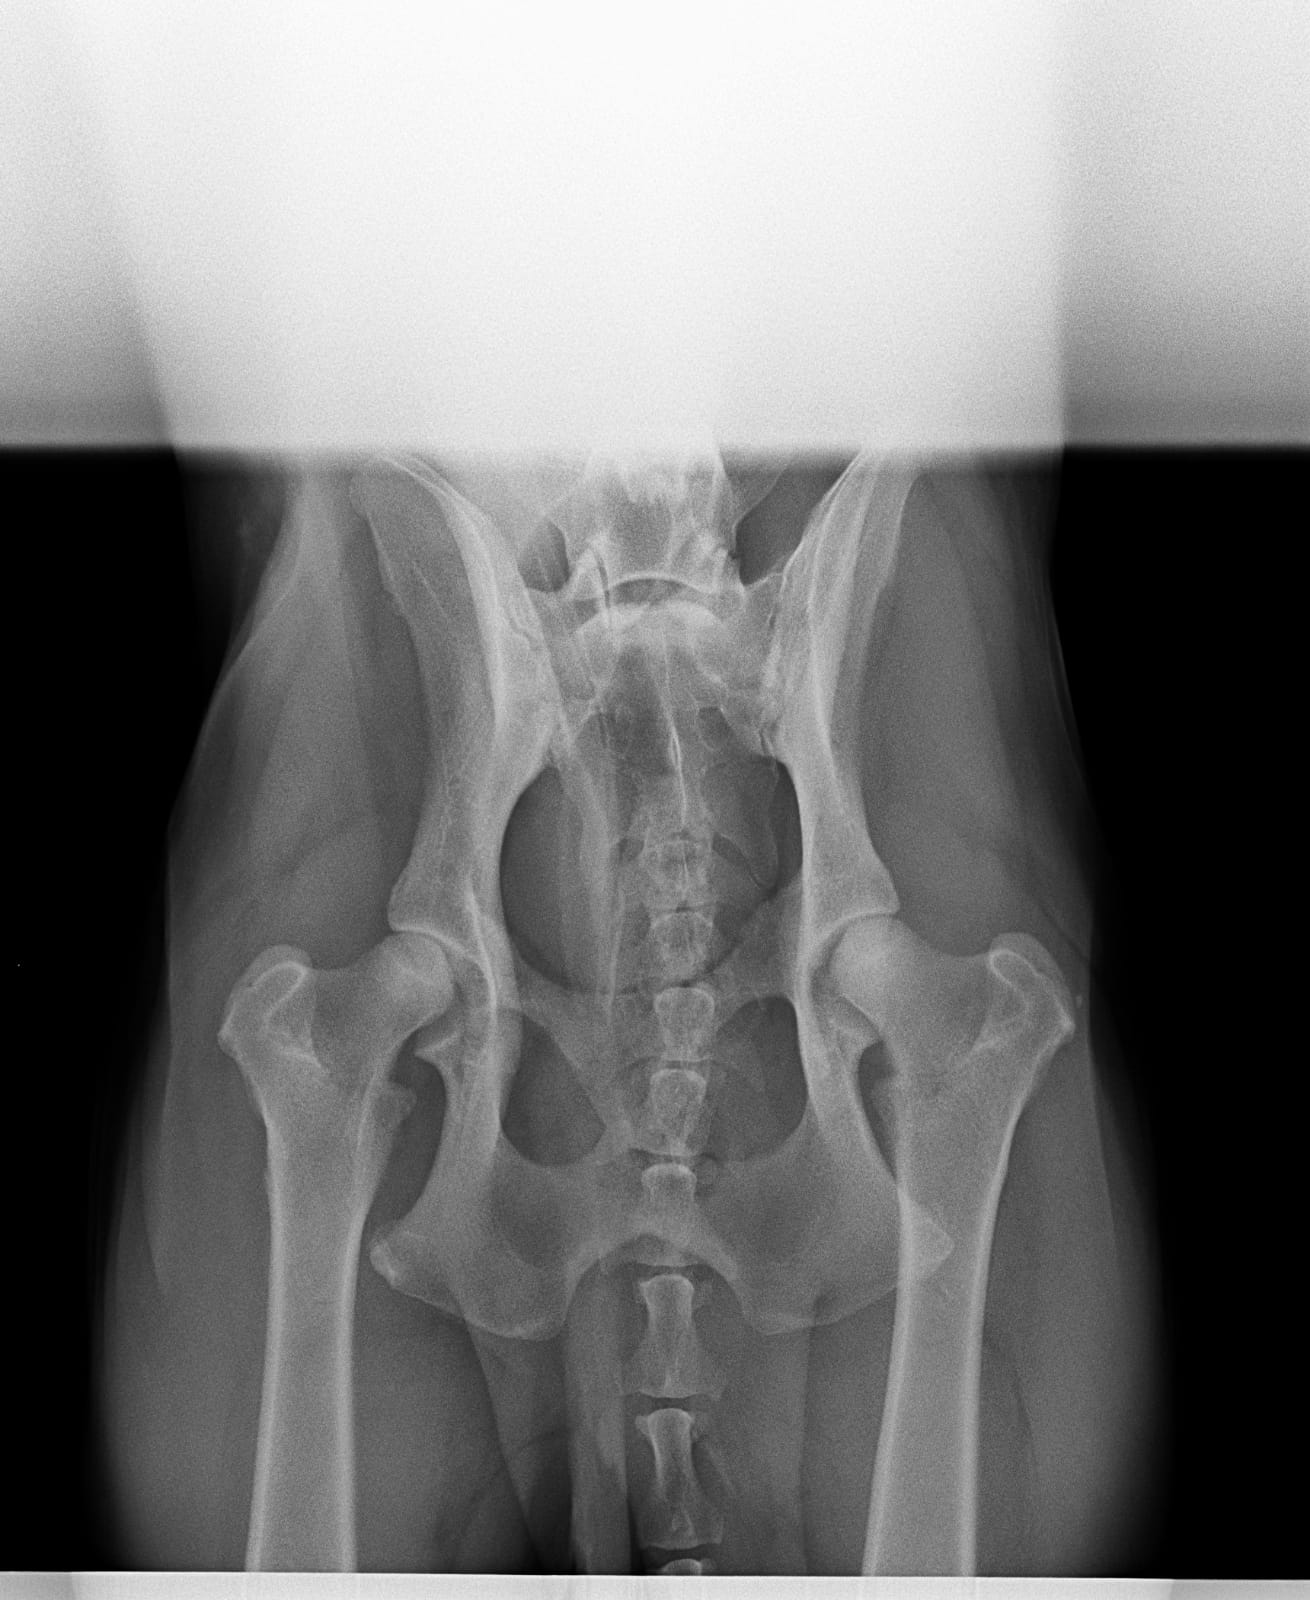

- Hüftgelenksdysplasie (HD)